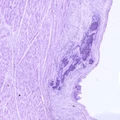

![]() | obrzęk jelita | 50%